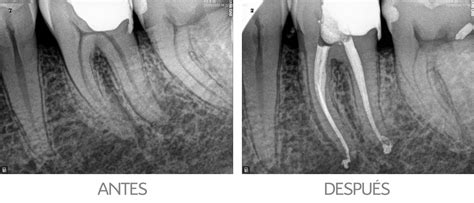

El primer paso es el diagnóstico y la evaluación inicial. El endodoncista examina y toma una radiografía del diente mediante rayos X para determinar si la pulpa está infectada y si la endodoncia es el tratamiento adecuado.

Tras eliminar la pulpa infectada, se procede a la obturación y sellado del conducto radicular. Después de limpiar y dar forma al espacio, se rellenan los conductos radiculares con un material biocompatible, normalmente un material parecido a la goma llamado gutapercha. La gutapercha se coloca con un cemento adhesivo para garantizar el sellado completo de los conductos radiculares.

Los conductos dentales deben ser sellados completamente hasta el ápice radicular (extremo de la raíz) para asegurar la efectividad a largo plazo del tratamiento de endodoncia y prevenir futuras infecciones.